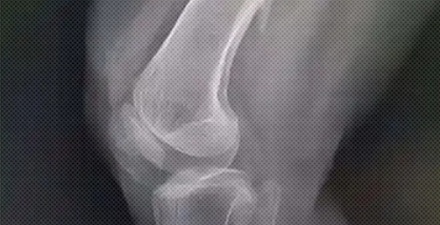

为什么医生会让骨折的病人等几天再手术?

得等伤口消肿,要不然手术的风险太高。

骨折后,伤口的肌肉等软组织会充血水肿。这时候手术,里面的肉往外鼓,伤口很难缝上。

就算硬是给缝上了,刀口两边的皮肤还可能会缺血坏死、切口崩开,甚至导致钢板外露。